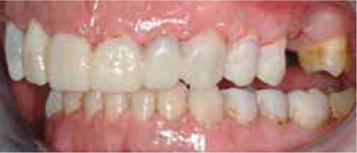

Bij het extraoraal onderzoek zie ik een lichte hypertrofie van de m. masseter. Intraoraal tref ik een ernstig versleten dentitie aan waarbij de slijtage niet passend bij de leeftijd kan worden genoemd (afbeelding 2-7 en tabel 1) .

Afb. 1

De heer H. bij de intake.

Afb. 2

Frontaal aanzicht van de dentitie.